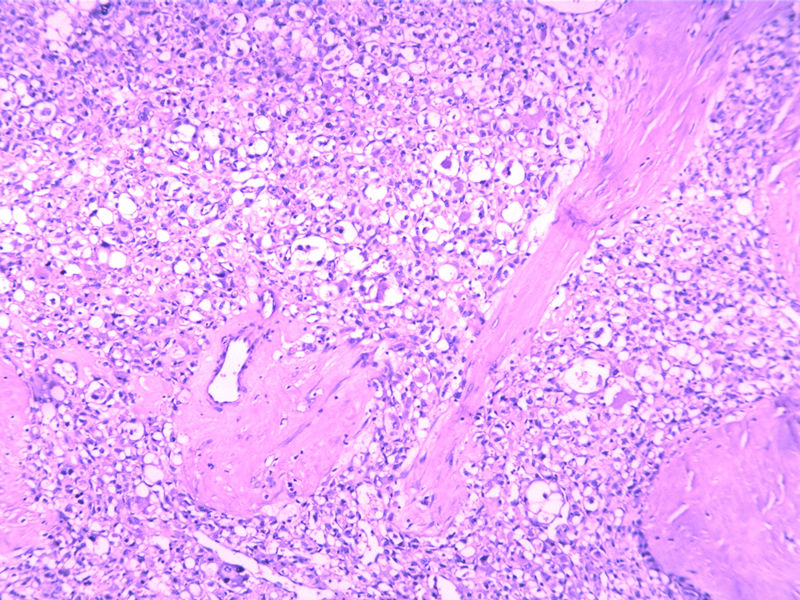

女30Y,大腿肿物5Y,直径3cm

生长位子比较深,浸润纤维间质之中,诊断圆形细胞脂肪肉瘤 ,查一下免疫组化,S-100,VimE。及PCK排除一下上皮来源的印戒细胞癌。

图片不清楚,至少要考虑和排查脂肪肉瘤。

Micro description

● Well circumscribed but non-encapsulated with infiltrative borders

● At least focal typical liposarcomatous areas

● Pleomorphic cells cover > 65% of cut surface with MFH-like, round cell liposarcoma-like (without vascular network), spindle cell liposarcoma-like or epithelioid cells (Mod Path 1999;12:722)

● Usually high grade with enlarged round to bizarre nuclei; tumor necrosis common; median 25 mitotic figures/10 HPF

● May have neutrophils within giant cells, hemangiopericytic foci, extra- and intracellular hyaline droplets